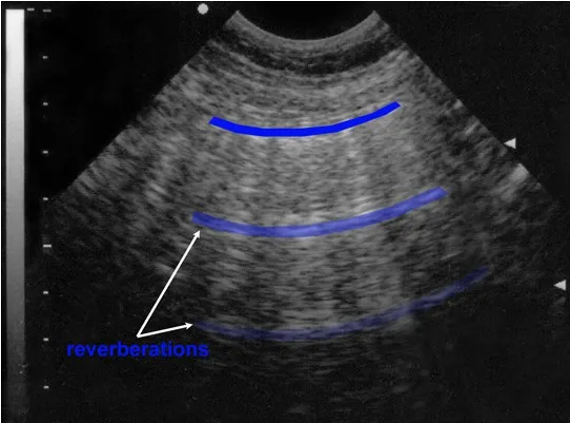

[10] Example ultrasound images with speckle noise(both), downward attenuation(both), shadows(blue regions left) and reverberation artefacts (blue lines right)

In addition to shadowing regions, two reflective objects can also cause reverberation artefacts when light bounces back and forth between them, causing a repeating pattern. In the right image they are highlighted with blue color and generally appear as repeating pattern with equal distance.